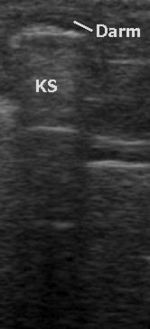

Zugänglichkeit von Organen

Alle wasserhaltigen, blutreichen Organe sind für den Ultraschall gut untersuchbar. Schlecht untersuchbar sind alle gashaltigen oder von Knochen bedeckten Organe, zum Beispiel der Darm bei Blähungen, die Lunge, Gehirn und das Knochenmark. Manche Organe sind im Normalzustand nur schwierig, im krankhaft vergrößerten Zustand dagegen gut erkennbar (Blinddarm, Harnleiter, Nebennieren).